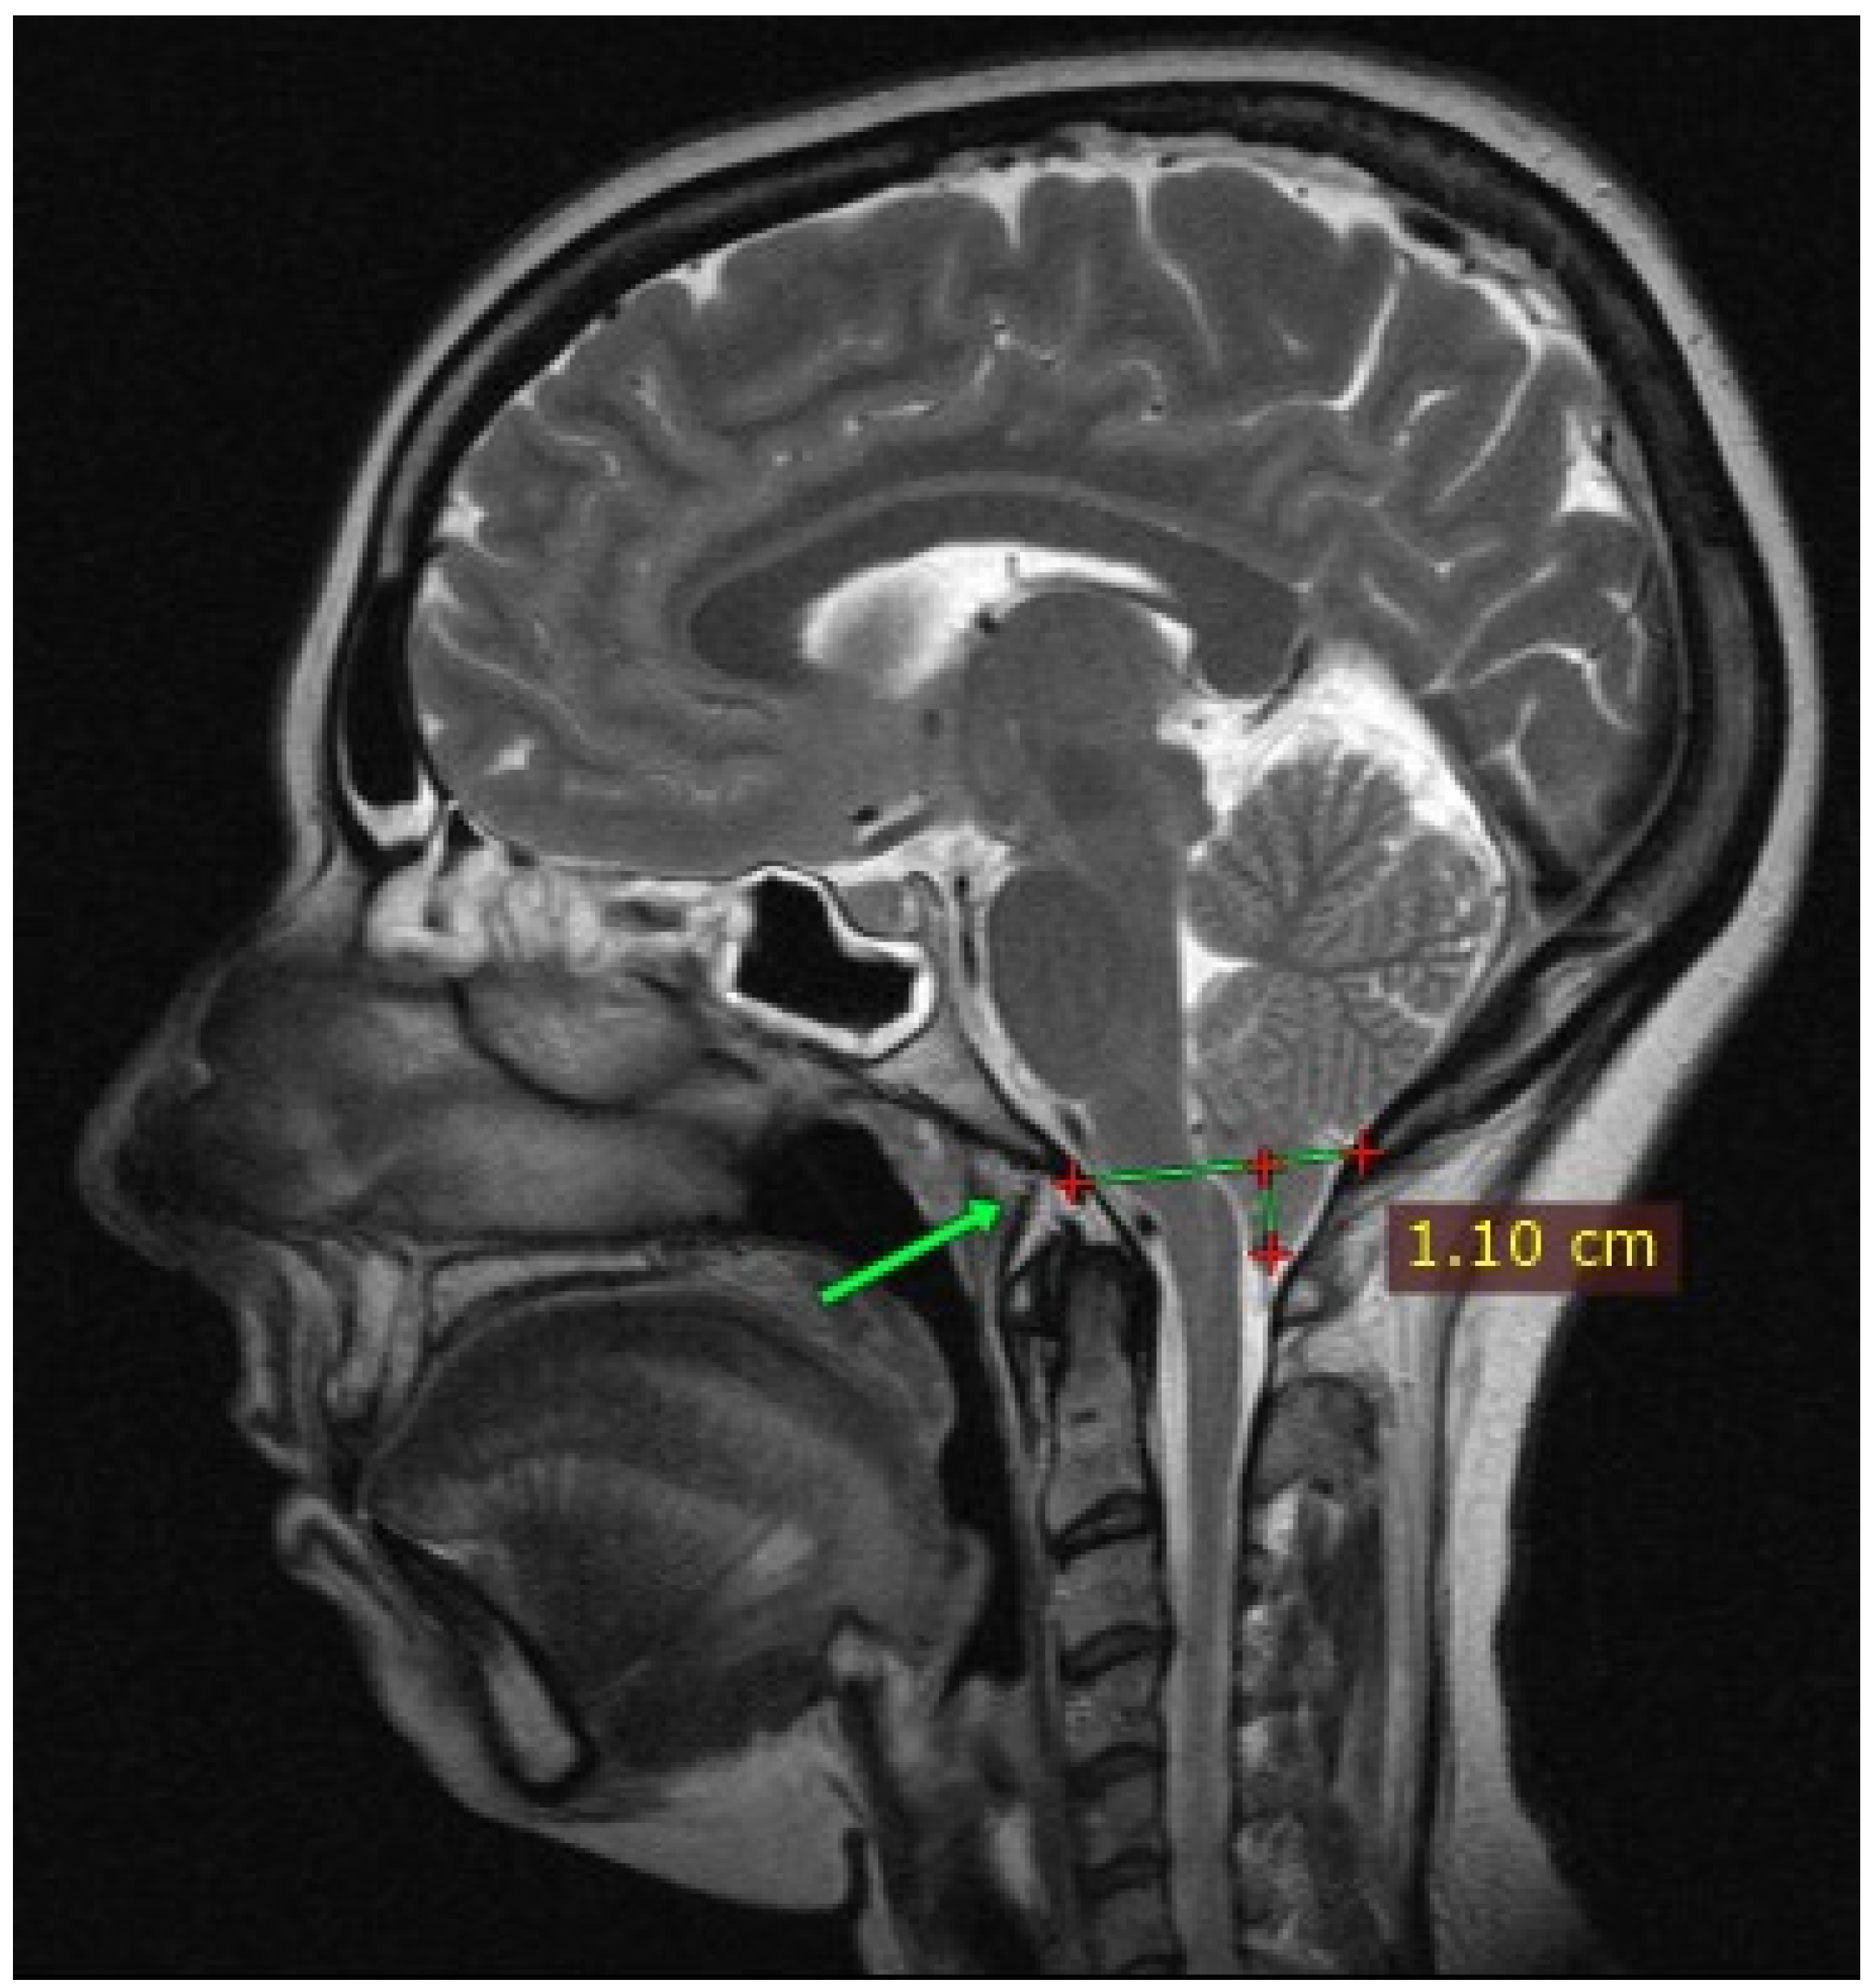

2. Case Presentation